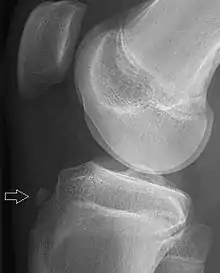

![]() | |

| Avulsion fracture of the proximal middle phalanx on the palm side | |